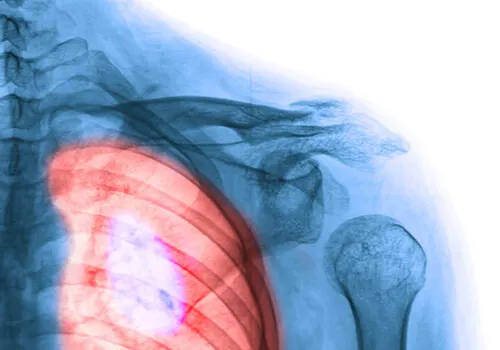

Cáncer de pulmón

El cáncer de pulmón es una de las formas más agresivas de la enfermedad oncológica, tanto en hombres como en mujeres. De hecho, según datos del Centro para el Control y Prevención de Enfermedades, causa más muertes que el cáncer de mama, colon y próstata.

El cáncer de pulmón se produce cuando las células que recubren los bronquios se ven alteradas o deterioradas, bien sea por los radicales libres del ambiente, factores genéticos o malos hábitos de vida.